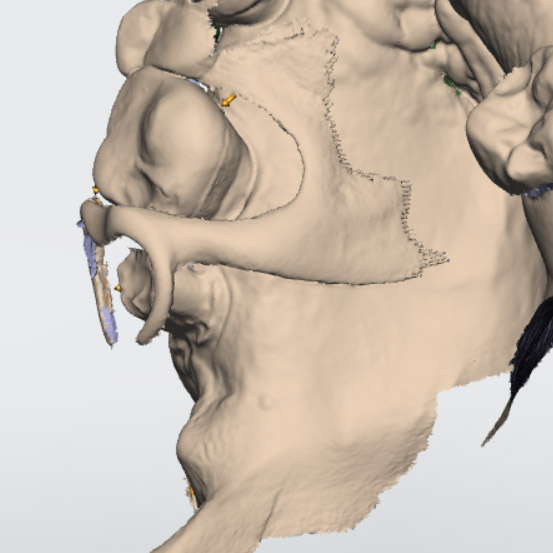

Hallmark Dental Laboratory Ltd. is a full-service dental lab that provides services to dentists across Canada. We specialize from dentures to crown & digital